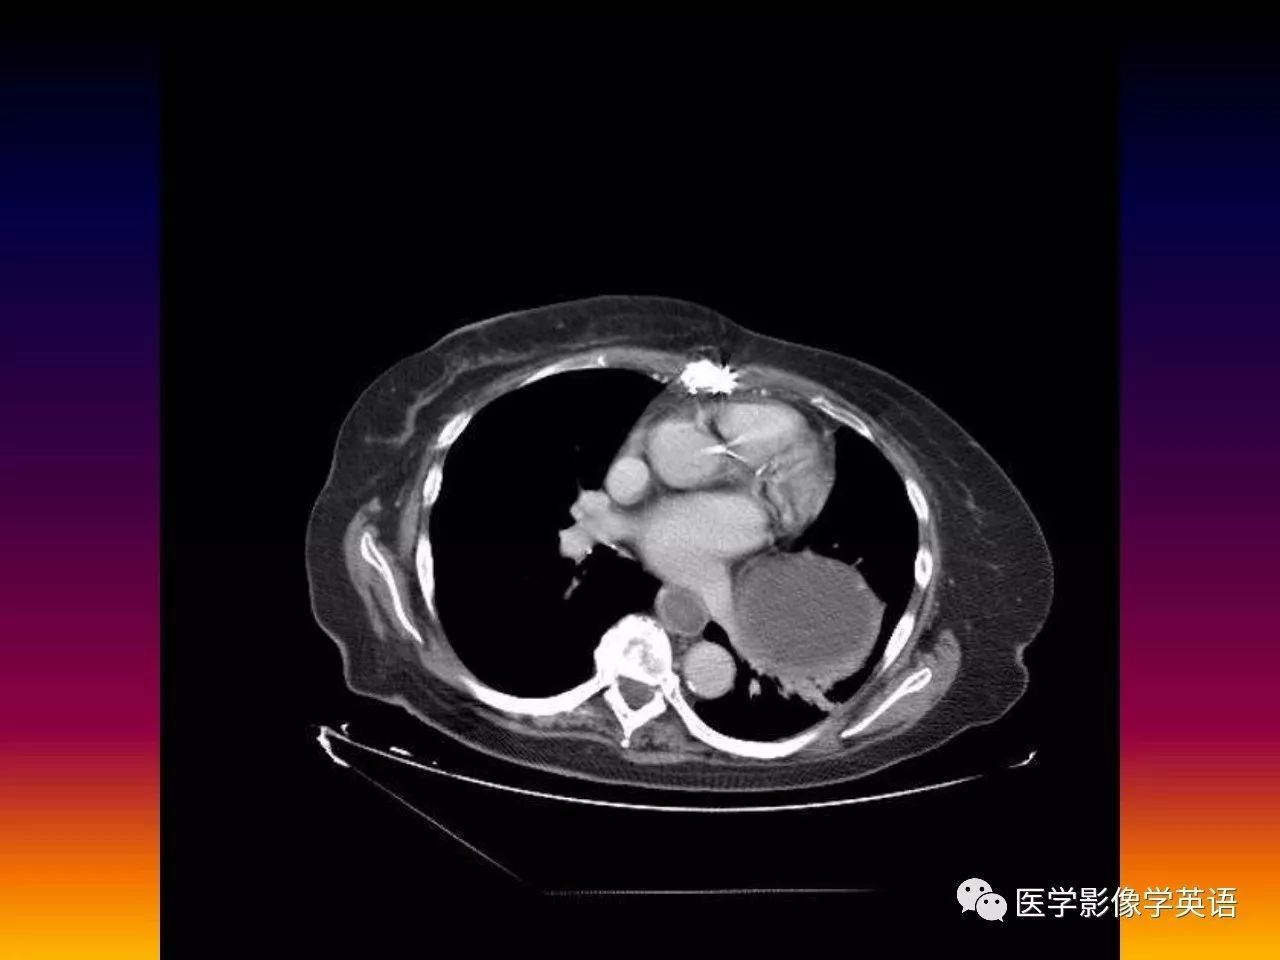

46. Organo-axial gastric volvulus

47. Organo-axial gastric volvulus

48. Organo-axial gastric volvulus